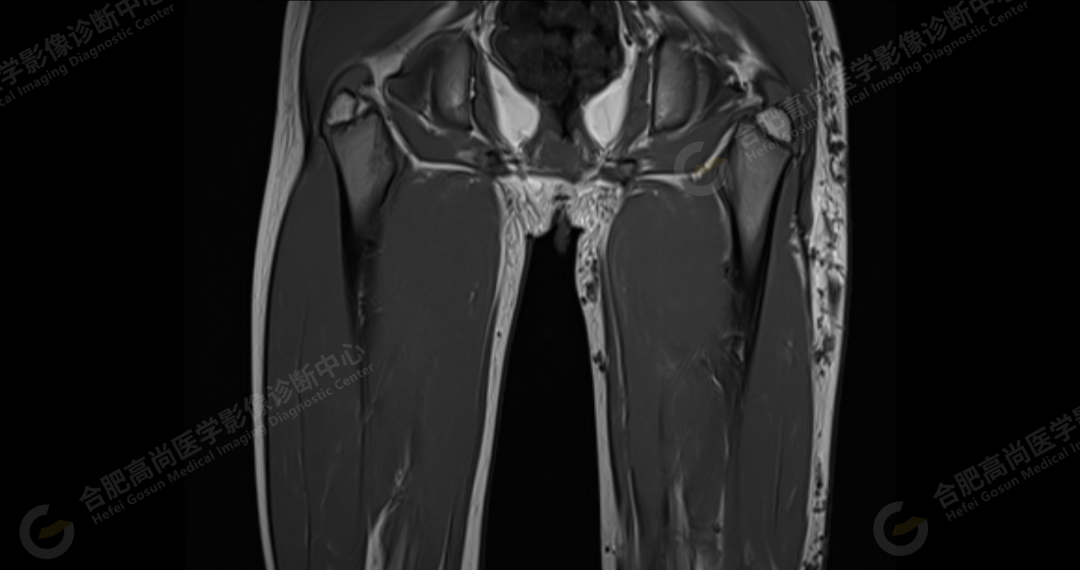

左侧髂骨内侧及闭孔内肌前方可见网格状异常信号影,边界欠清,T1WI 呈低信号,T2 压脂呈高信号,病变连续,延伸至臀肌内;左侧臀肌间隙及皮下、左大腿后部肌肉群及皮下、左膝前外侧及腘窝皮下、左小腿后侧皮下累及比目鱼肌及内外侧腓肠肌、左内外踝皮下、左足背足底及左足肌间隙内可见大片状、结节状弥漫性异常信号影,形态不规则,分布不均匀,边界不清,T1WI 呈低信号,T2WI 压脂后病灶呈高信号,部分病灶内可见网格状低信号,左足部肌间隙增宽,第 2-4 跖骨稍受压,骨质结构完整。左髋关节、膝、左踝关节间隙正常,无明显狭窄及增宽,关节面光滑,关节腔内无积液,左股骨、胫腓骨及踝部各组成骨骨质结构完整,未见明显异常改变。

左侧盆腔及下肢皮下及部分肌间隙内漫状血管瘤,请结合临床。